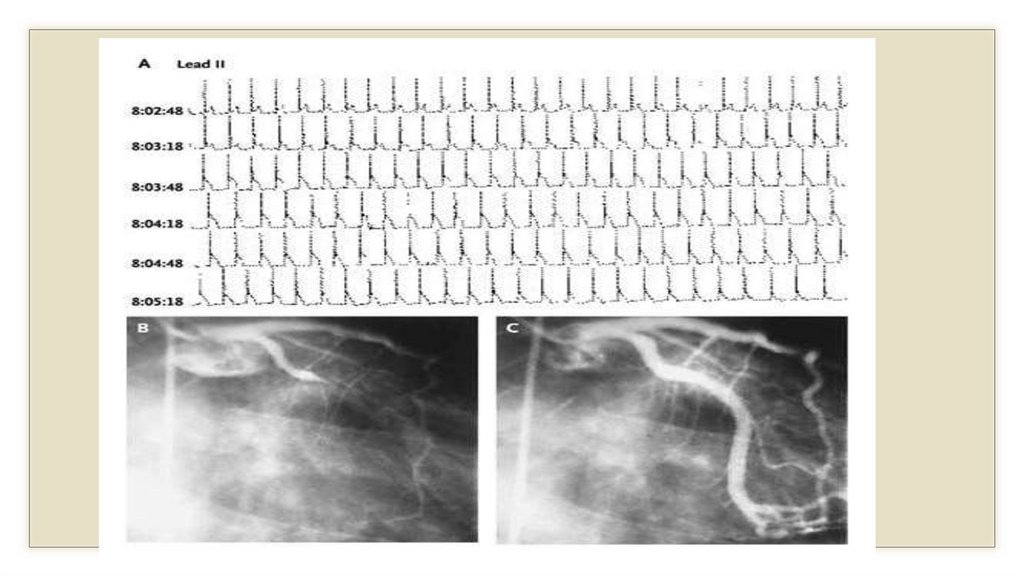

Дополнительные методы.

◦ 8.Коронароангиография (КАГ): определяет проходимость коронарных

сосудов (стеноз) и др.

◦ 3. КАГ - коронароангиография